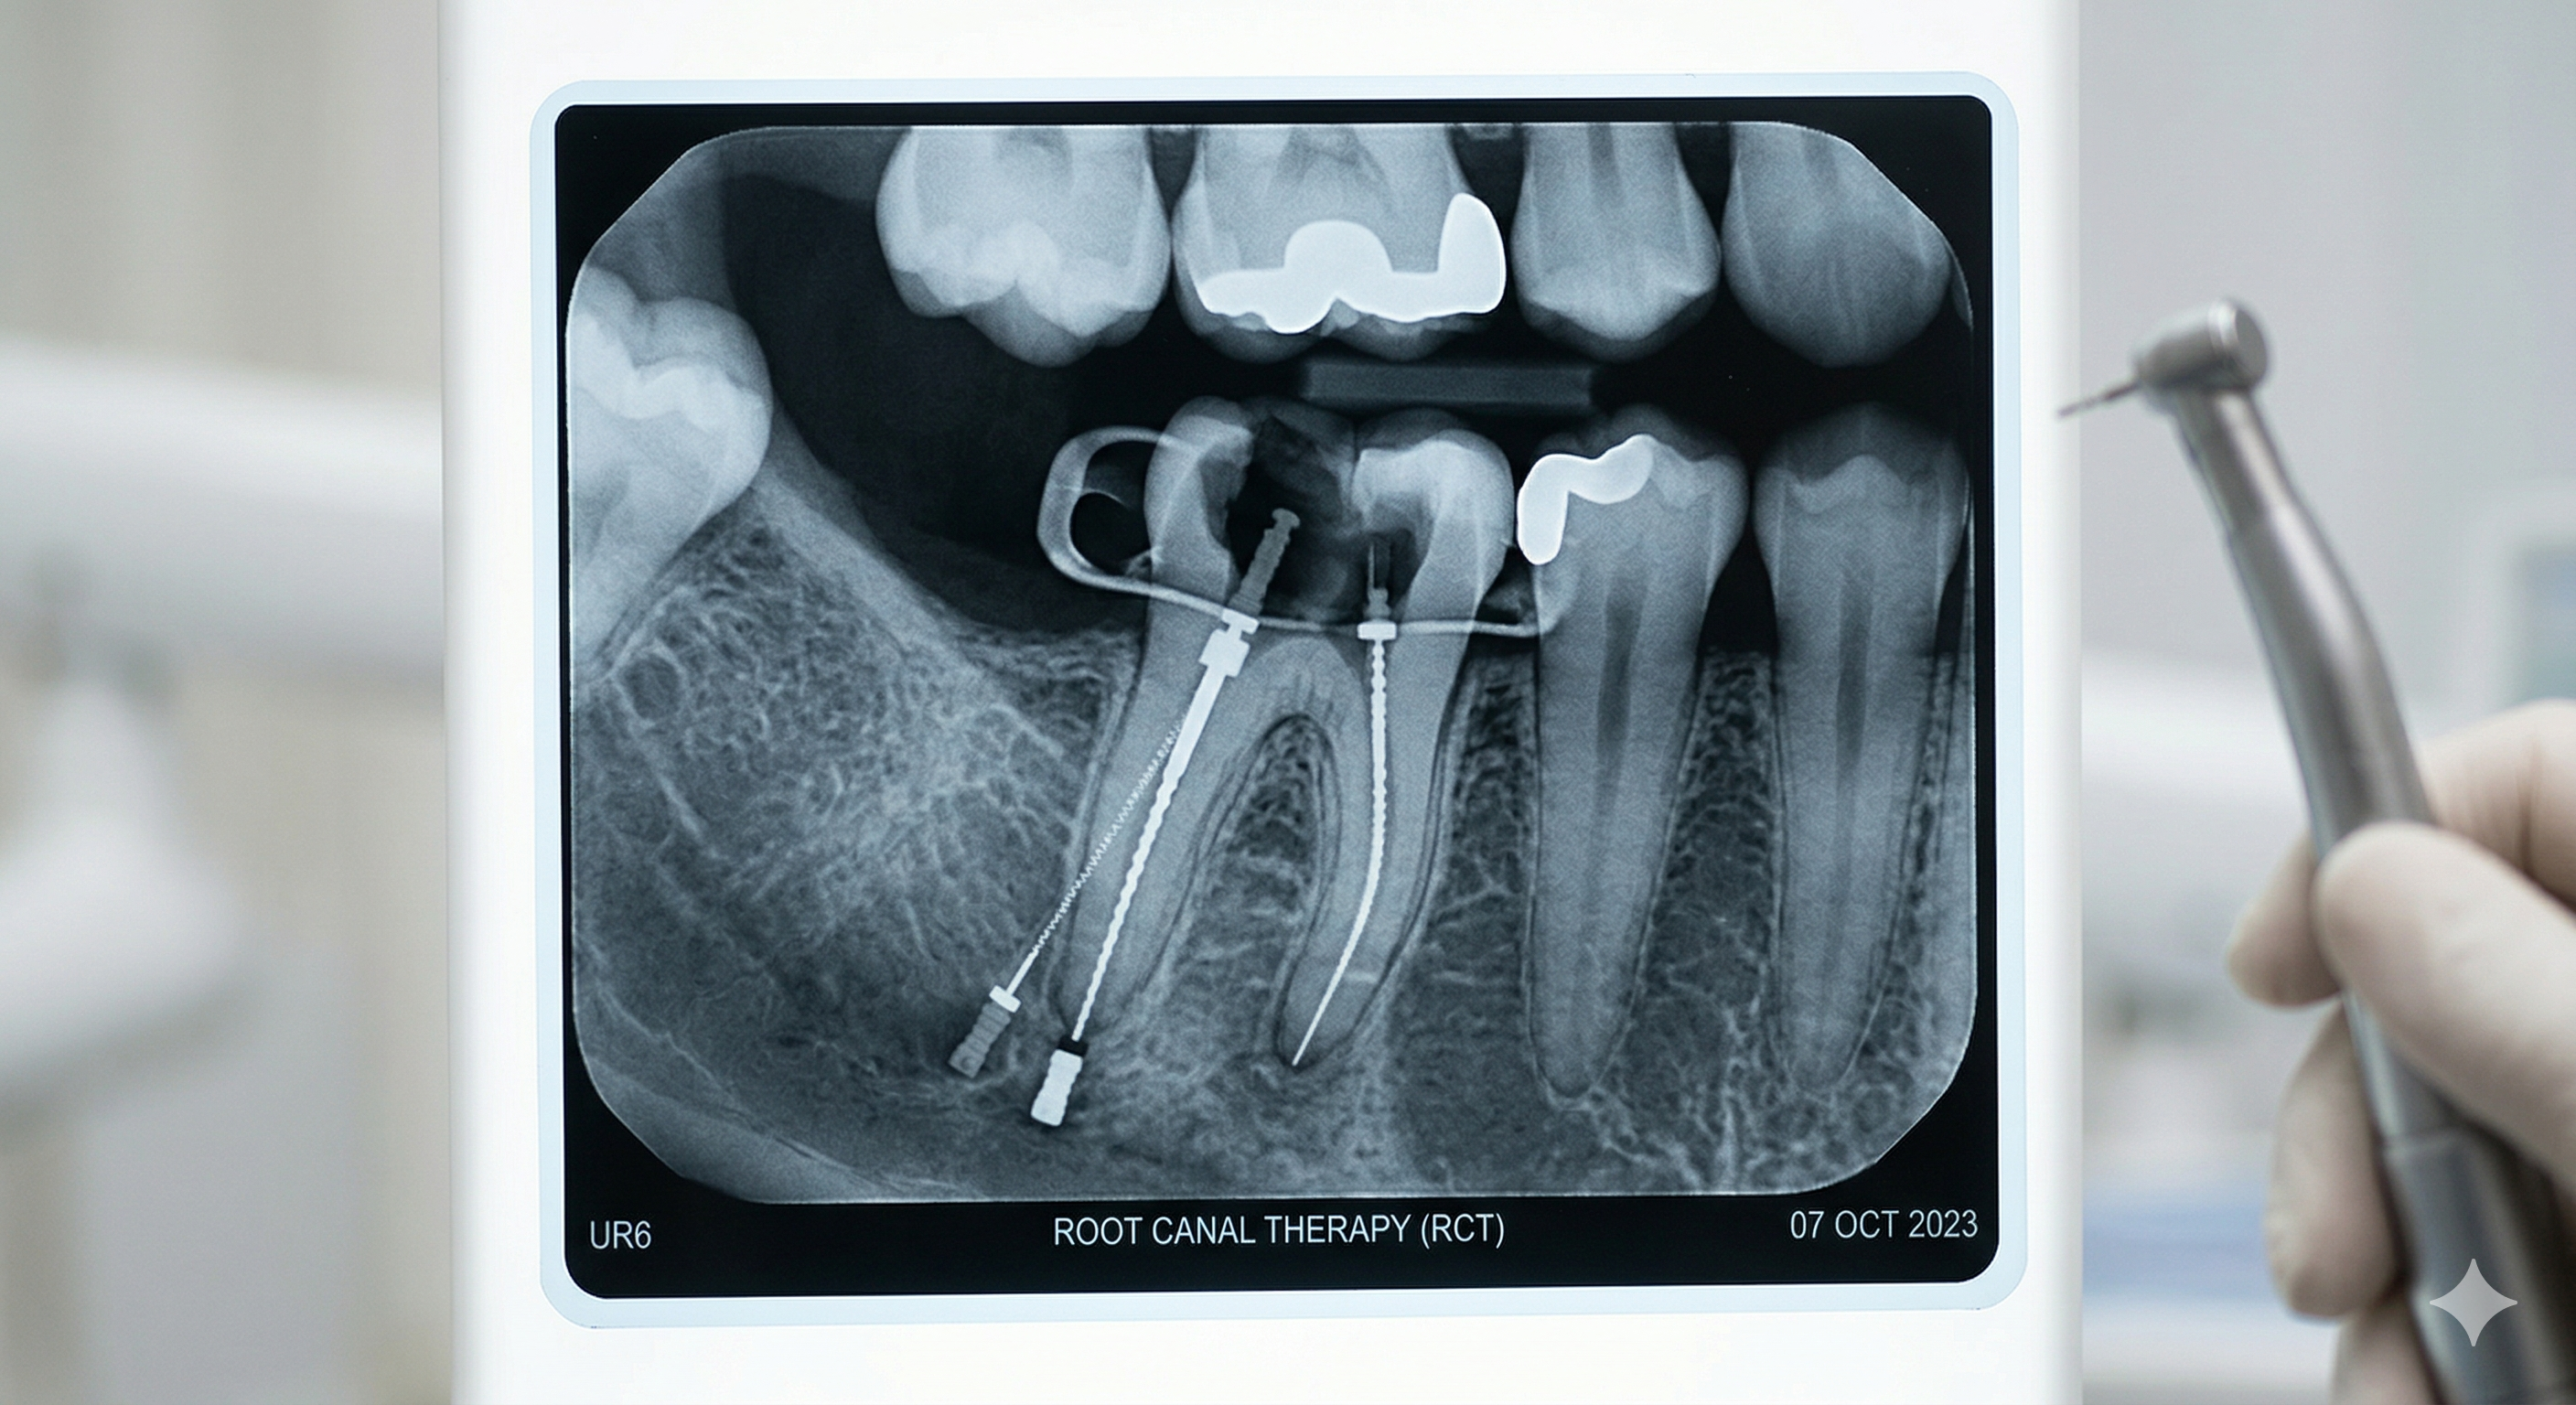

Dr Kwa Zheng Kang

Specialist Endodontist

Dr. Kwa is a specialist in Endodontics with over a decade of clinical experience. After obtaining his DDS in 2012, he pursued advanced training in Spain to master microscope-aided dentistry. Known for handling complex root canal cases and surgical retreatments, Dr. Kwa is also a prominent international speaker, having conducted workshops across Asia and the Middle East. His academic work is published in peer-reviewed journals, and he is recognized globally for his excellence in clinical techniques.